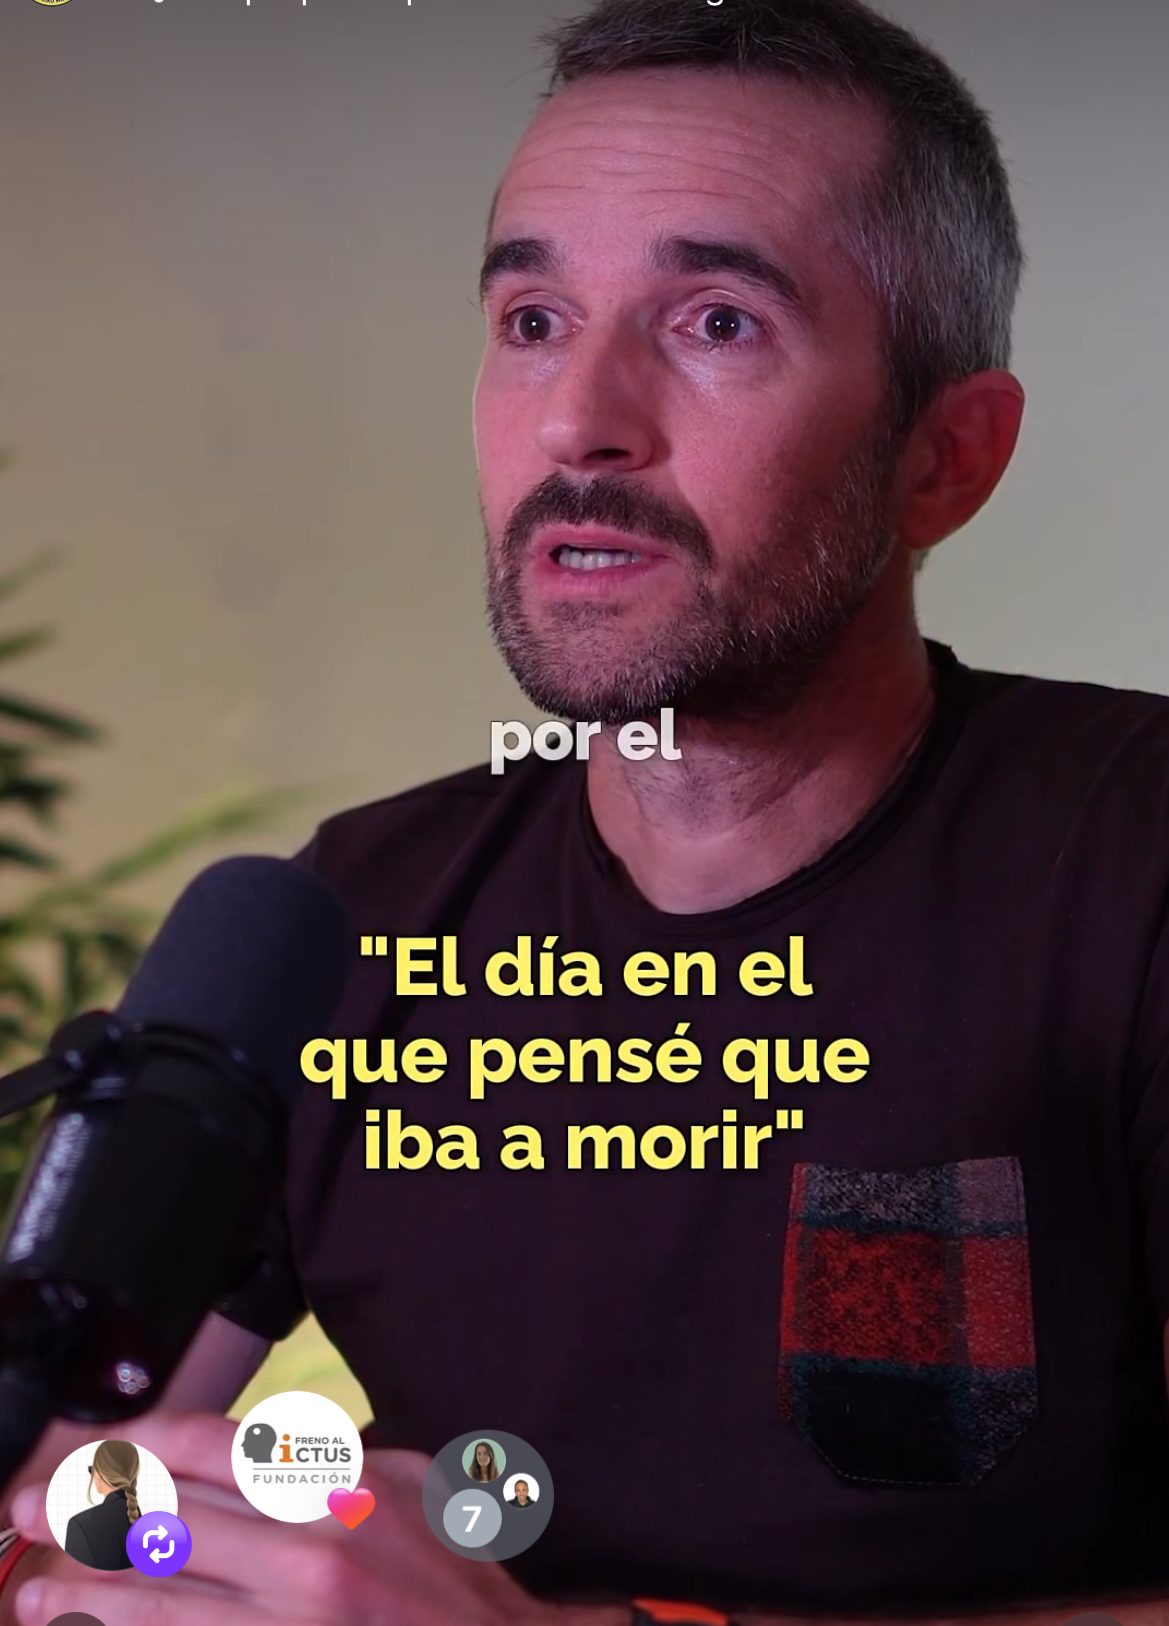

Un día normal de trabajo estuve a segundos de morir por un ictus agudo, y mi vida cambió para siempre.

Decidí contar mi historia porque vi que ayudaba. A que a otras personas no les pase lo mismo. También a quienes ya lo sufrieron, y se sienten incomprendidas, solas y maltratadas.

Mi historia

El 23 de noviembre de 2022 era un día normal. Entré en casa a mediodía, una hora antes de la reunión. Saqué el móvil para cargarlo en el cable que está en la cocina, pero lo metí de nuevo en el bolsillo derecho. Eso me salvó la vida.

Si no llego a tener el móvil, me habría muerto.

Si lo llego a guardar en el bolsillo izquierdo, también.